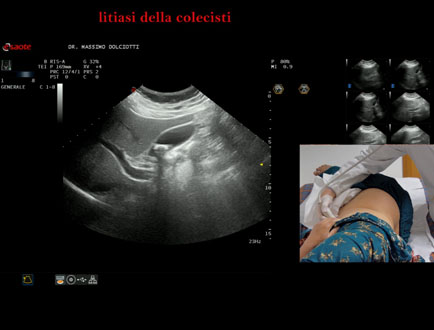

Data inserimento: 13/10/2025

Ecografia del: 07/10/2025

Strumento: Esaote MyLab Eight

Sonda: Convex Multifrequenza 1-8 MHz

Età Paziente: F 49 anni

Motivazione dell'esame: follow up per litiasi della colecisti dopo trattamento con acido ursodesossicolico.

Commento all'esame: le immagini ed il video documentano nel lume della colecisti, immagine iperecogena, delle dimensioni di 16,1 mm, con cono d'ombra posteriore, mobile al decubito, da ricondurre a litiasi.

Conclusioni: litiasi della colecisti (gallstone).

Presentazione: Dr. Massimo Dolciotti - Ancona

Elaborazione digitale: Andrea Dini - Ancona